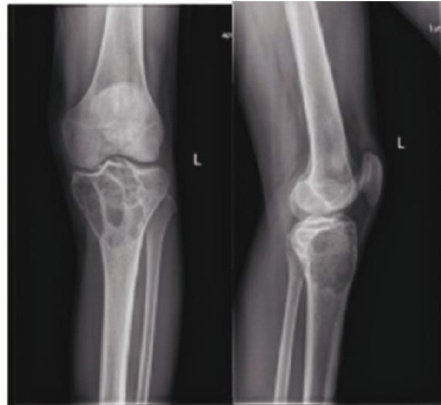

中图分类号:R738.1 文献标志码:B DOI:10.3969/j.issn.1003-1383.2025.12.014 骨巨细胞瘤(giantcell tumorofbone,GCT)为低度恶性或潜在恶性的肿瘤,由Jaffe于1940年首次发现,为常见的原发性骨肿瘤之一,其来源尚不清楚,有研究认为起源于非成骨性结缔组织,具有较强侵袭性,对骨质的溶蚀破坏作用大[1],可穿过骨皮质形成软组织包块